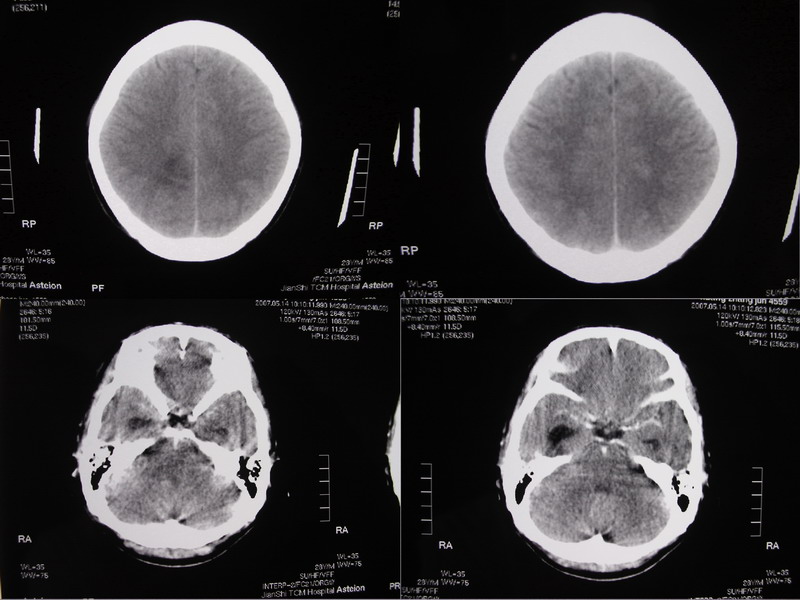

以下是引用余辉在2007-5-14 17:03:00的发言:[br]右侧脑室颞极后方可见高密度块状影,颞极呈杯口状推挤前移,右侧大脑脚及丘脑上部受推挤向对侧移位,右丘脑区结构紊乱,增强扫描病灶有不规则强化,以下部颞极后方为著。胼胝体压部及右枕叶视辐射区低密度改变,右基底节区低密度改变,双侧脑室不对称积水征象,意见:1颞极后方—右丘脑区占位性病变,如室管膜瘤等2脑血管疾病如moyamoya,局部脑血管畸形等3脑膜炎等后遗改变,建议mr及脑血管造影检查[br][br][本贴已被 余辉 于 2007-5-14 17:05:26 修改过]

以下是引用千里草在2007-5-14 15:54:00的发言:[br]考虑:1、双侧梗阻性脑积水;[br] 2、右侧基底节区缺血性脑血管疾病。

以下是引用ssmmxx在2007-5-14 18:05:00的发言:[br]颞极后方—右丘脑区占位性病变,如室管膜瘤等2脑血管疾病如moyamoya,局部脑血管畸形等

以下是引用qiuleiyu在2007-5-14 18:43:00的发言:[br]支持;1,交通性脑积水(病脑后遗征?)2,右基底节及胼骶体压部低密度灶伴轻度占位表现,结合年龄考虑moyamoya,建议dsa.[br]